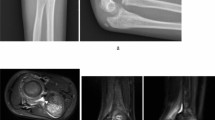

The Picture Archiving and Communication System (PACS) version used was AnnetPACS V 2.0.01. All imaging data were independently measured by a senior orthopedic resident who had undergone three months of systematic radiology training. To ensure the reliability of the measurement data, ten X-ray films were randomly selected and measured by both a senior associate chief orthopedic doctor and an attending doctor from the imaging department to authenticate the measurements. Three researchers used identical computer programs with consistent measurement software. The inner-epiphyseal ulna length (IEUL) was defined as the distance from the tip of the olecranon to the midpoint of the distal epiphyseal plate of the ulna (red line). The inner-epiphyseal radial length (IERL), represented by the yellow line in Fig. 1, was defined as the distance between the midpoints of the radial head epiphysis and the distal radius epiphysis. The inner-epiphyseal ulna-radius length ratio was calculated as follows:

The epiphyseal plate and ossification center of the ulna do not develop proximally until 9 years of age, and the epiphysis is not visible on radiographs. As a result, it is difficult to measure the lengths of the ulna and radius radiologically, and all measurements excluded the ossification center and epiphyseal plate.

A total of 432 children aged 1–15 years with ulna and radius X-ray films were included, with a minimum of 30 children in each age group. There were 255 boys (59.0%) and 177 girls (41.0%). The left forearm was measured in 236 children (54.6%), while the right forearm was measured in 196 children (45.4%). The mean inner-epiphyseal ulna-radius length ratio was 1.094, with a standard deviation of 0.024, and the range of values was 1.0336 to 1.168. The 95% medical reference range was 1.047 to 1.141, both the ulna and radius lengths increased with age, their length ratio at the epiphyseal plate remained relatively constant across age groups (Fig. 2).